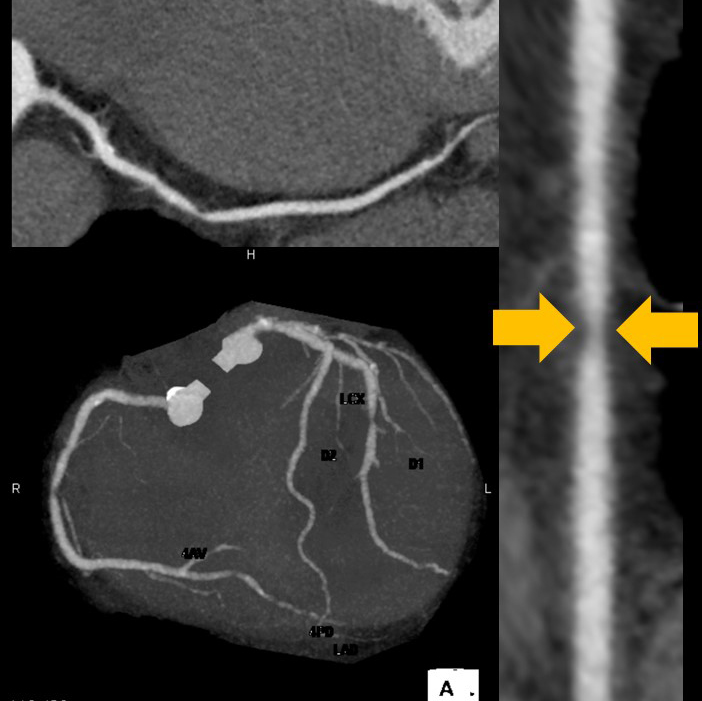

下の画像のように体内を断面(輪切り)にして観察できます。画像(1)は頭部のCT画像で、中の白くなっている部分が脳出血といわれる状態です。画像(2)は心臓のCT画像で冠動脈といわれる血管が狭くなっていないか(黄矢印)、石灰化といわれる状態になっていないかを検査できます。またCT画像を加工することにより3Dといわれる立体的な画像で観察することも可能です。

(2)心臓CT(冠動脈造影)